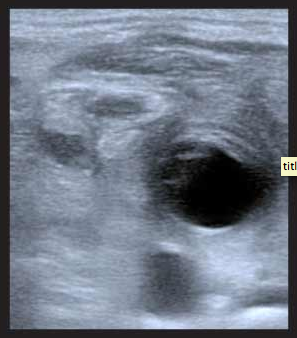

In this month’s issue of EP Monthly, they describe a case of a 50 year old with a history of diabetes and heroin use on home IV antibiotics for tarsal osteomyelitis with gradual onset fo left sided neck pain without fever or difficulty swallowing, or sore throat. She has pain with movement of her neck and her oropharynx is clear. Hmmmm, so the diagnosis is not presenting itself and whenever that happens to me, I gra the ultrasound machine to see if it can provide more information – just as they did. They get the below image with compression of his left neck with the linear probe:

What do you think? Well, to find out what it is and read about the technique and excellent pearls and pitfalls to this bedside ultrasound application, click here.